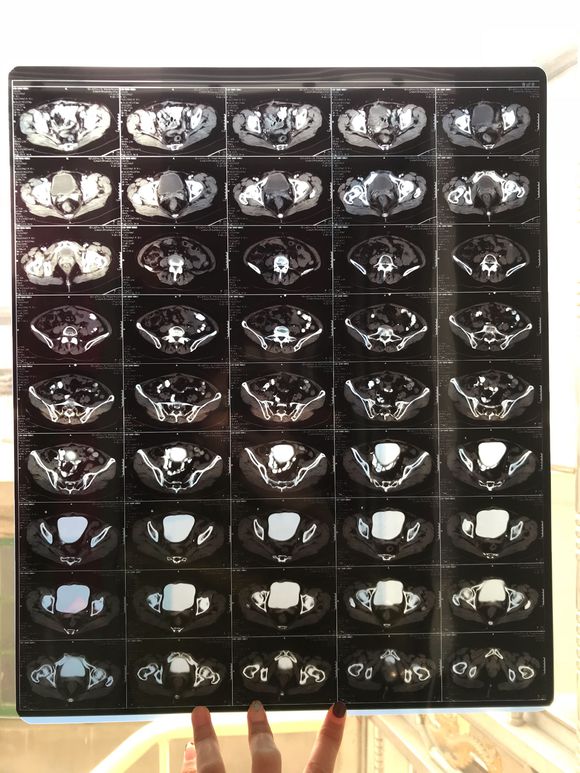

和你的故事 02019-04-09 患者家属我妈妈的病理结果报告,3期c1,大家可以帮忙看看吗,跪求了!我很急,谢谢!想知道是否严重,目前等术后出院后去肿瘤医院...

0人关注 4个回复 3458次浏览 -